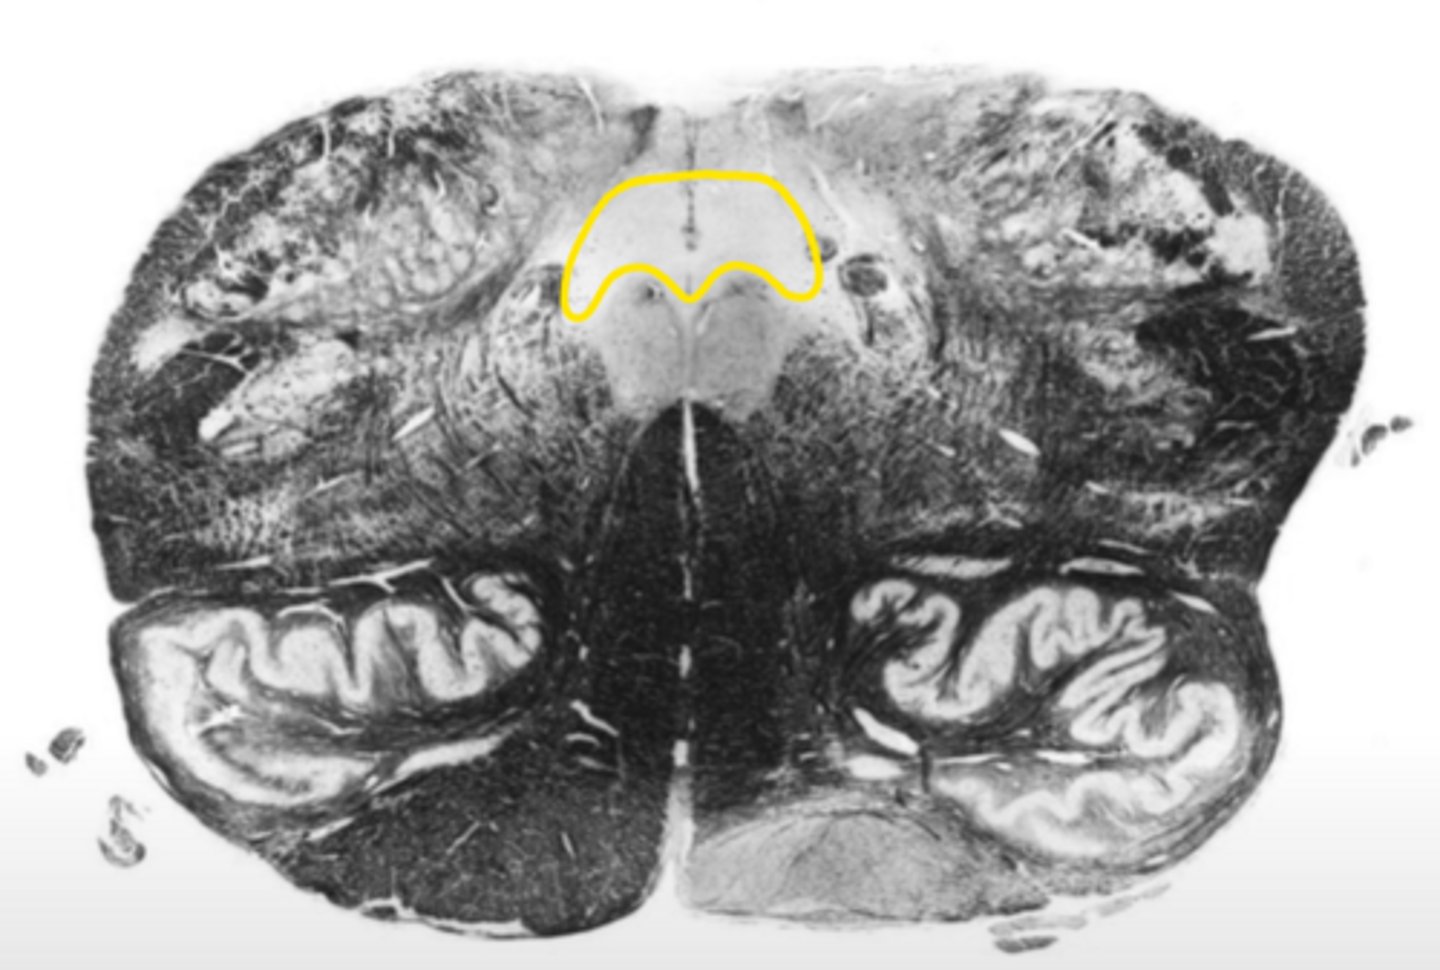

open medulla

ID the brainstem level